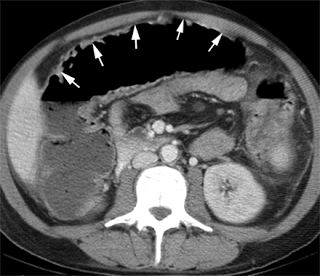

Aspect TDM en coupe axiale d'

une toxic megacolon par cause maladie de Crohn . La

colon transverse distendue et la paroie du colon est

epaissisement oedemateuse |

Toxic megacolon

: Aspect radiologique TDM en coupe axiale . |